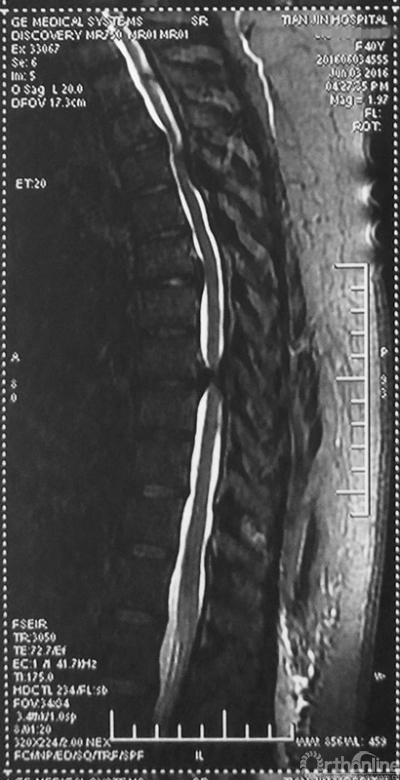

家人曾带她辗转当地治疗,因病情复杂没有得到有效的治疗,于是慕名找到天津医院脊柱外科二病区主任苗军博士诊治,当苗军主任看到躺在担架上的刘女士痛苦的表情和渴望健康的眼神,他决定收她入院为其进行手术治疗。入院检查发现,刘女士患有多节段胸椎管狭窄症,以胸8-9节段严重,椎管狭窄达80%,脊髓已严重变性。

术前MRI

术前CT